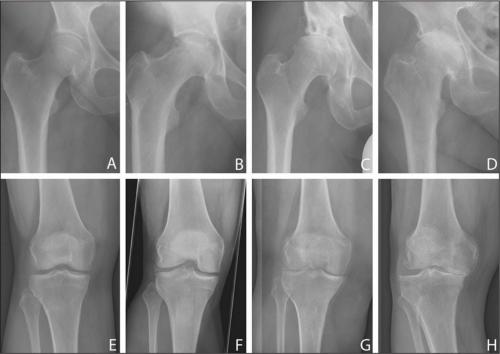

- Коксартроз . Локализуется в тазобедренном сочленении. Причиной поражений, приводящих к истощению и последующей дегенерации хряща и изменения костной суставной поверхности, является недостаточное питание сустава и неимоверная длительная нагрузка на ноги.

- Гонартроз поражает коленный сустав. Дегенеративно-дистрофическому изменению подвергается гиалиновый покров сустава, сужается суставная щель. Происходят деформация и перестроение костной ткани с образованием шипов – остеофитов. Нарушает подвижность колена.